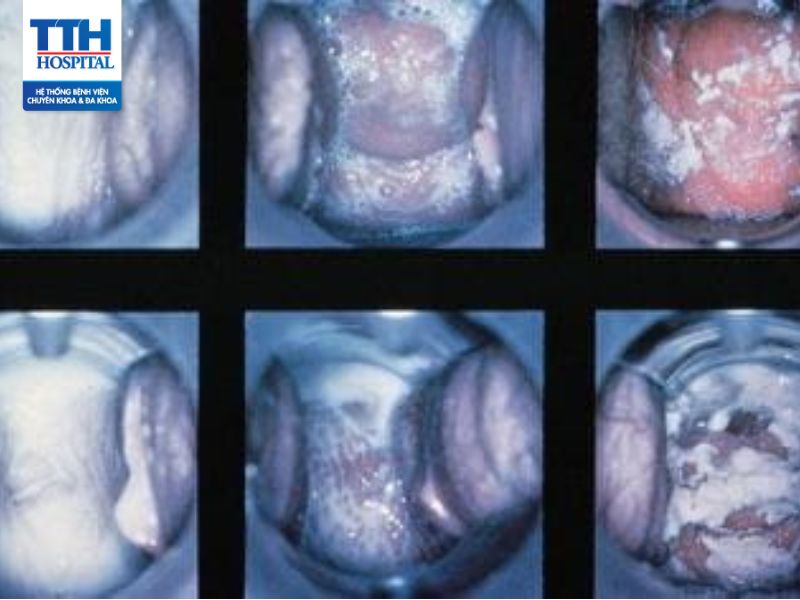

Viêm âm đạo là gì?

Viêm âm đạo là một tình trạng viêm nhiễm trong âm đạo, là cơ quan sinh dục nữ nằm ở bên trong cơ thể. Viêm âm đạo có thể gây tiết dịch bất thường kèm mùi do vi khuẩn, nấm, vi rút hoặc các tác nhân gây kích ứng khác.

Dấu hiệu viêm nhiễm âm đạo

Một số dấu hiệu thường gặp của viêm nhiễm âm đạo bao gồm:

Ngứa và rát trong vùng âm đạo.

Đỏ, sưng và viêm đỏ ở vùng âm đạo.

Dịch âm đạo có màu, mùi và đặc tính khác thường, có thể là dịch đặc, màu trắng, và có thể có mùi hôi.

Đau hoặc rát khi tiểu tiện hoặc quan hệ tình dục.

Có thể có cảm giác đau buốt hoặc đau nhức ở vùng âm đạo.

Phương pháp chẩn đoán viêm âm đạo

Để chẩn đoán viêm âm đạo, bác sĩ có thể sử dụng một số phương pháp sau:

Kiểm tra lâm sàng

Bác sĩ sẽ thực hiện một cuộc phỏng vấn chi tiết về các triệu chứng bạn đang gặp phải, lịch sử y tế và tình trạng sức khỏe chung. Sau đó, họ sẽ tiến hành kiểm tra lâm sàng để kiểm tra các dấu hiệu và triệu chứng của viêm âm đạo.

Thu thập mẫu để tiến hành xét nghiệm

Bác sĩ có thể thực hiện lấy mẫu dịch âm đạo để kiểm tra xem có sự tăng trưởng bất thường của vi khuẩn, nấm hoặc tế bào viêm nhiễm để làm xét nghiệm.